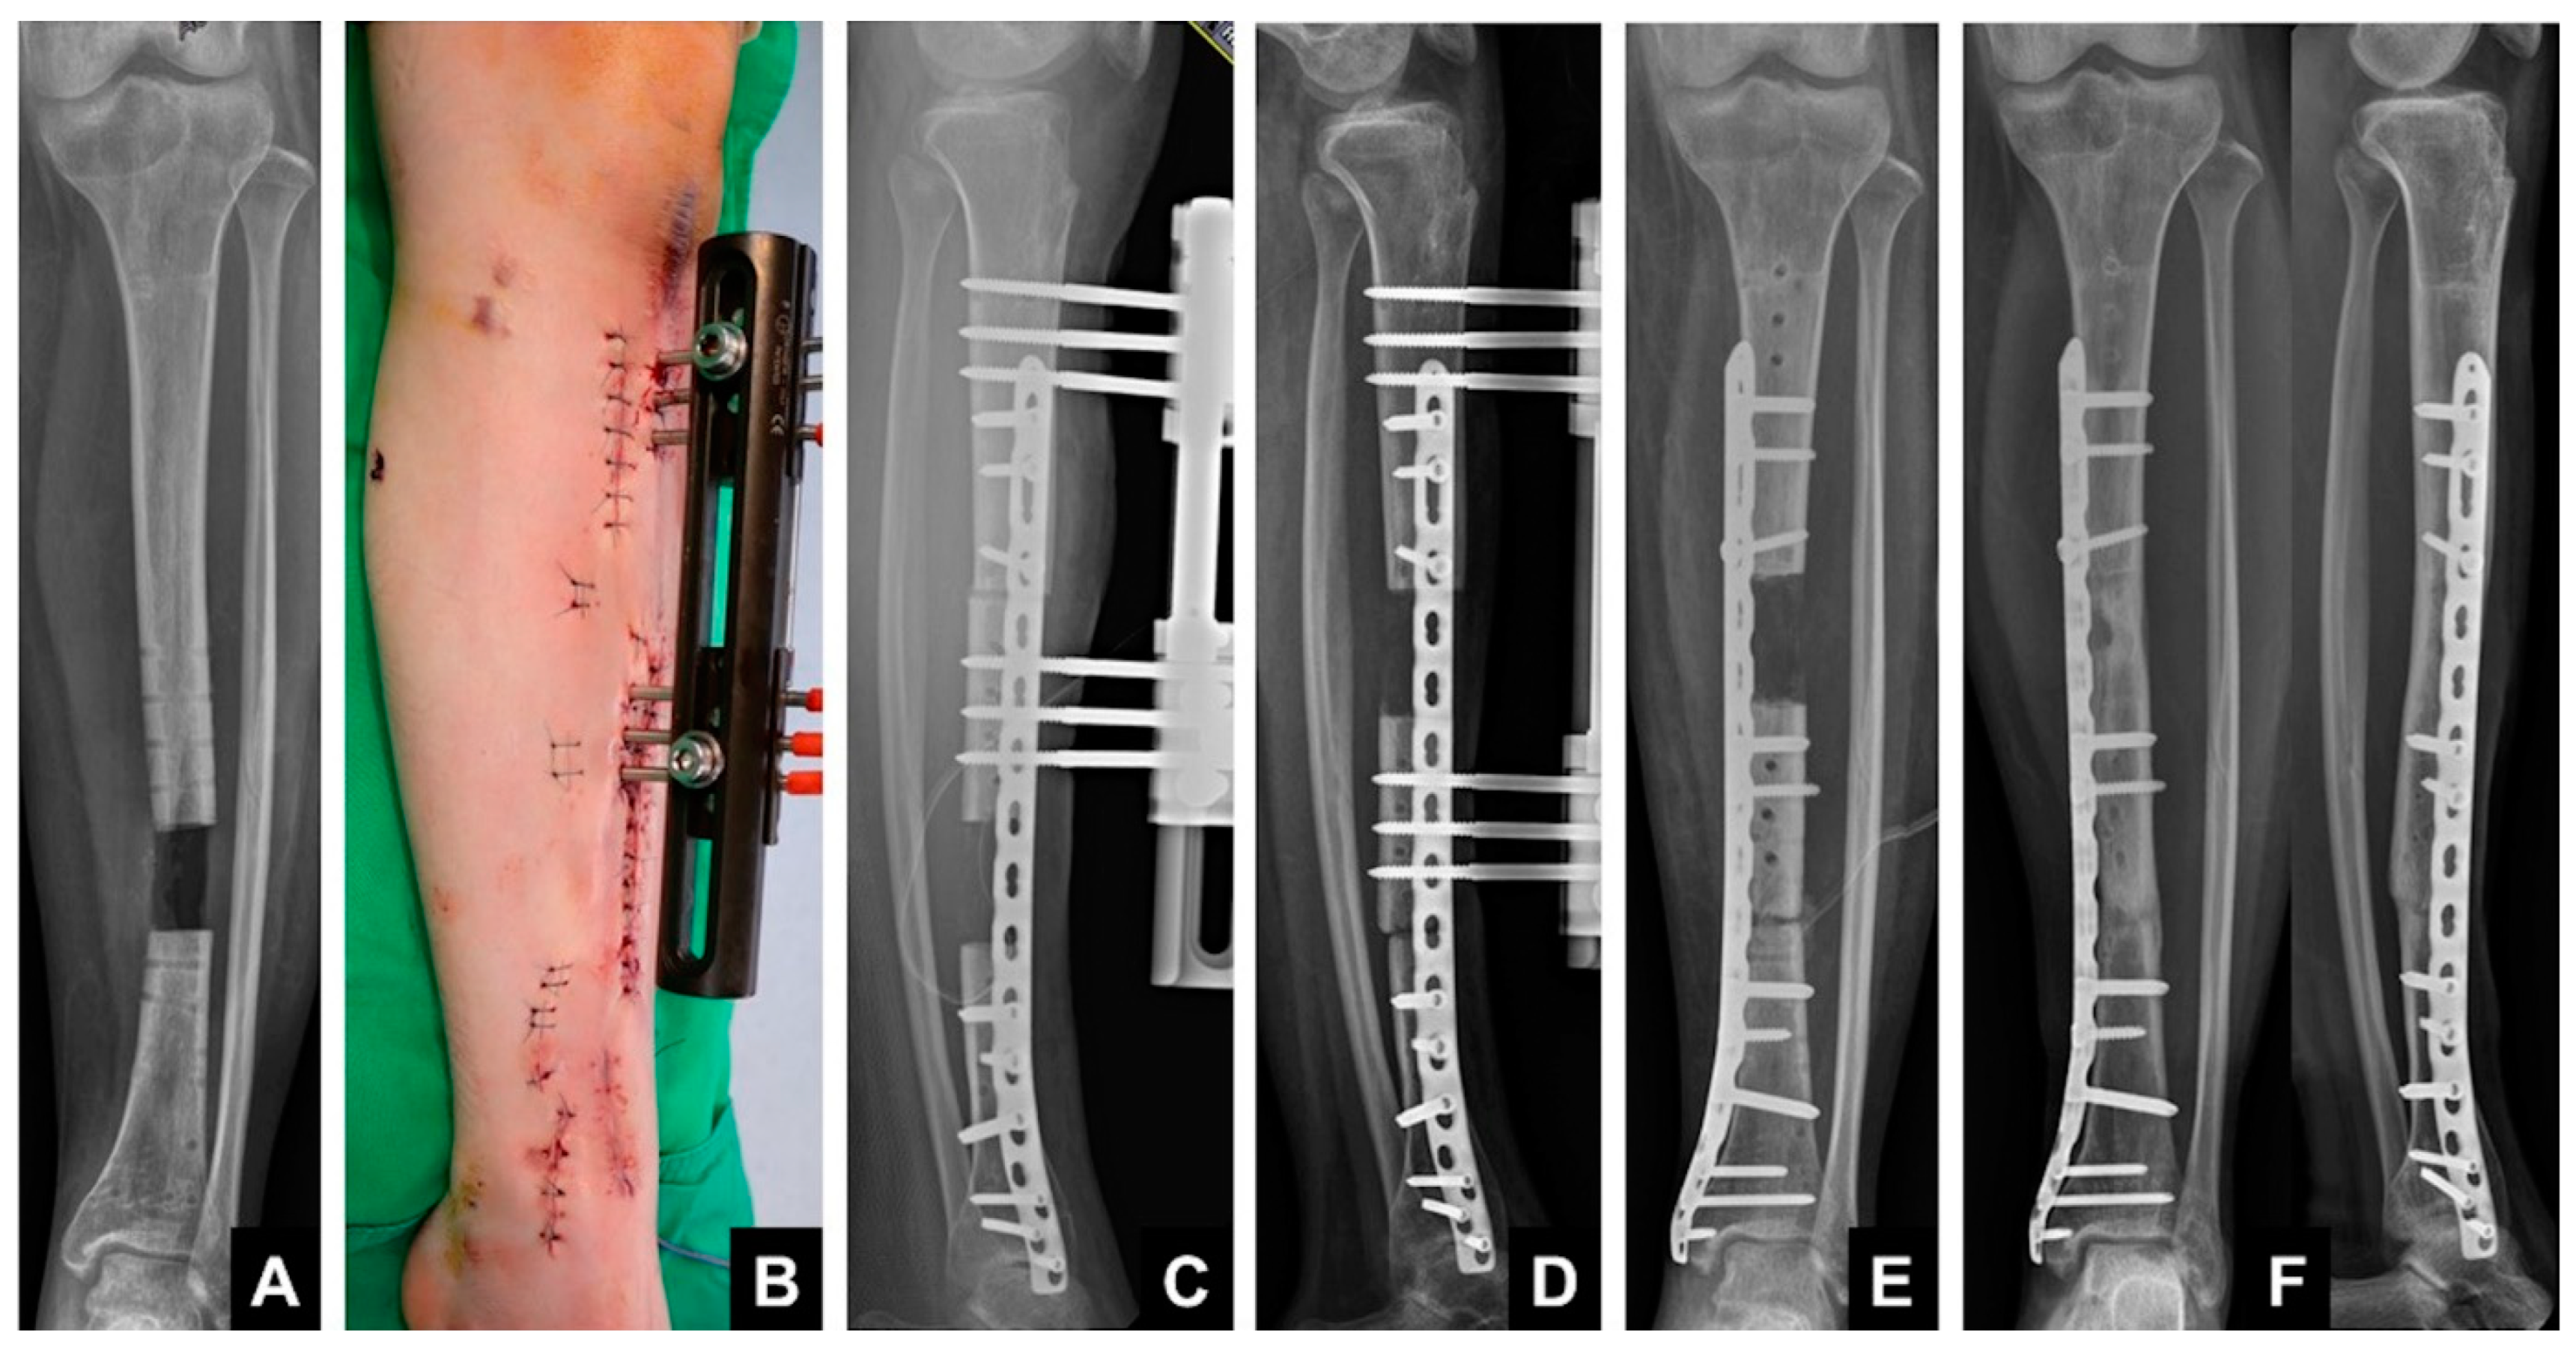

2.4. Plate-Assisted Bone Segment Transport (PABST)

- Kahler, O.U. Plate-assisted segmental bone transport with a lengthening nail and a plate: A new technique for treatment of tibial and femoral bone defects. Unfallchirurg 2018, 121, 874–883. [Google Scholar]

- Barinaga, G.; Beason, A.M.; Gardner, M.P. Novel Surgical Approach to Segmental Bone Transport Using a Magnetic Intramedullary Limb Lengthening System. J. Am. Acad. Orthop. Surg. 2018, 26, e477–e482. [Google Scholar] [CrossRef]